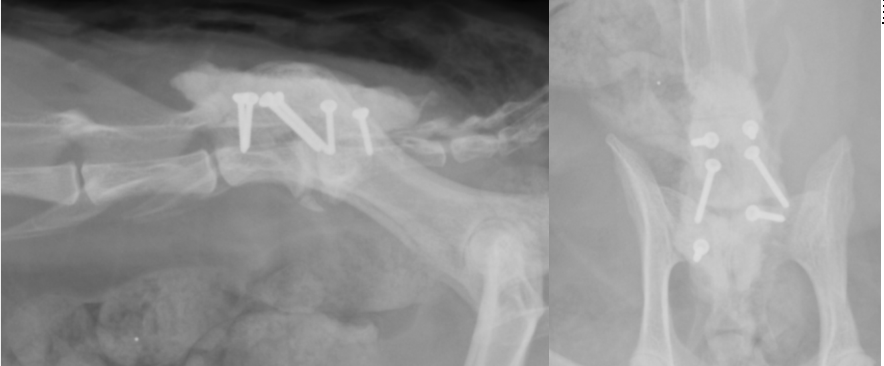

手術では背中からアプローチし、骨と靭帯を除去したのちに腹側の圧迫があればそれも除去します(減圧)。

その後に腰を曲げ伸ばした状態でスクリューと骨セメントを利用して固定します。

斜めに入っているスクリュー2本が経関節固定のスクリューで、他の4本は骨セメント固定用のスクリューです。

スクリューのヘッドを覆っているものが骨セメントです。

真ん中の2つが経関節固定のスクリューで、前後2本ずつ入っているのが骨セメント用スクリューです。

それを覆う四角形のものが骨セメントです。

スクリューにはロッキングスクリューを利用しています。

圧迫が解除されたらスクリューをうち、セメントによって固定します。

スクリューとセメントで固定されています。